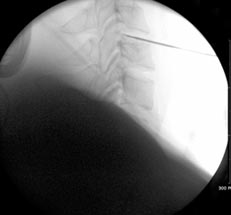

경추부수핵성형술

- 고주파에서 나오는 열을 이용, 튀어나온 디스크를 줄어들게 하는 치료법

당일 혹은 1박 2일 입원, 국소마취로 30분~45분 시술, 퇴원 후 바로 일상생활 가능 터지지 않은 허리 및 목 디스크 팽윤증, 디스크내장증에 시행